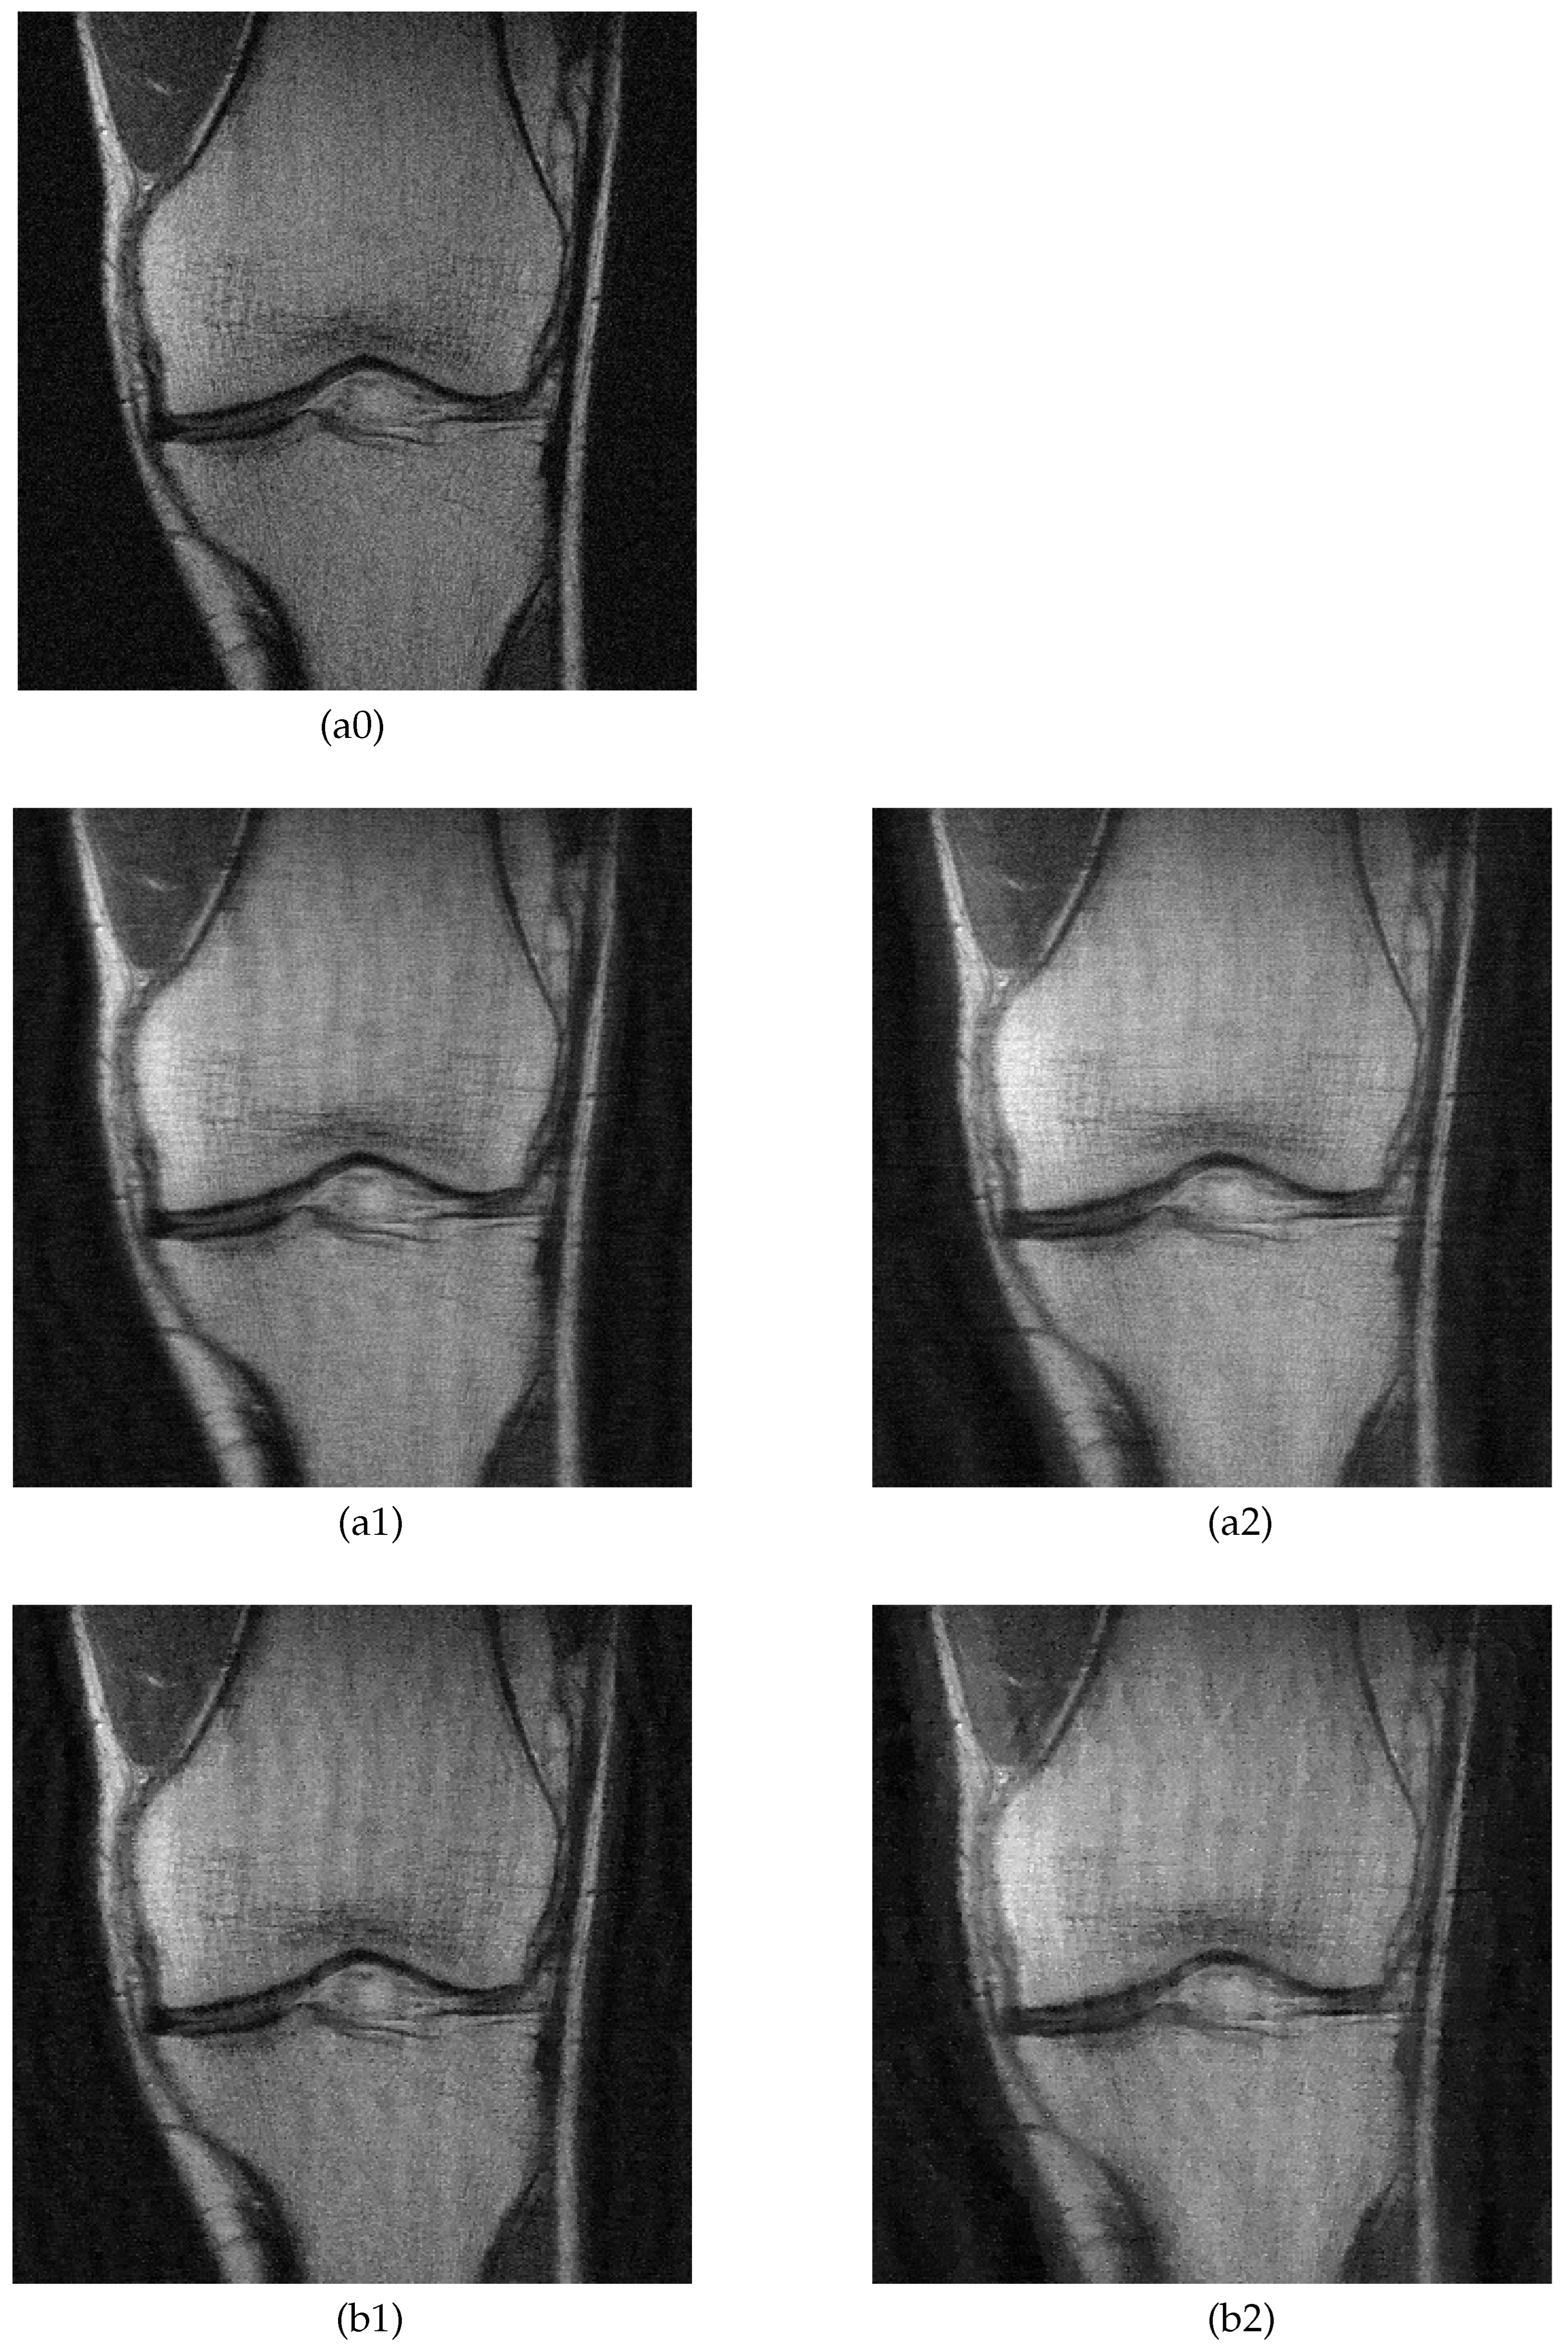

5.2. MRI Image Recovery

| Proposed | TV Method | |||||||

|---|---|---|---|---|---|---|---|---|

| PSNR | SSIM | PSNR | SSIM | |||||

| 4× | 8× | 4× | 8× | 4× | 8× | 4× | 8× | |

| Knee A | 28.5 | 26.4 | 0.657 | 0.570 | 28.2 | 24.5 | 0.615 | 0.538 |

| Knee B | 28.4 | 26.1 | 0.635 | 0.535 | 27.8 | 24.1 | 0.625 | 0.541 |

| Brain A | 27.7 | 24.1 | 0.642 | 0.524 | 26.7 | 22.3 | 0.637 | 0.493 |

| Brain B | 27.7 | 24.6 | 0.668 | 0.494 | 26.8 | 22.7 | 0.644 | 0.474 |